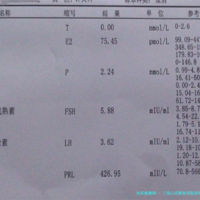

影响成功率的因素:病人自我的健康状态是干扰成功率的重要要素。年纪是重点,大体上,女性年龄越小,卵子质量越好,成功率越高。比方25-30岁的女性,美国三代试管婴儿成功率可能接近80%;而35岁以上,成功率会逐渐下降,到40岁左右,成功率可能降至30%-40%。再者,病人的子宫环境、激素水对等同样会对成功率发生影响。